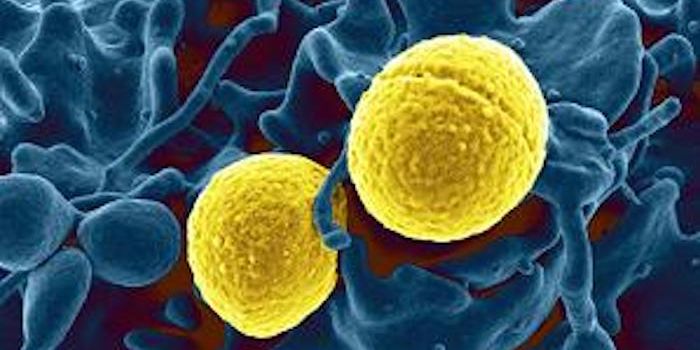

FEB 16, 2025MicrobiologyBacterial pathogens can cause serious infections. So many of them are becoming resistant to the effects of antibiotics t ...

FEB 05, 2025MicrobiologyAntibiotics are a crucial tool in the fight against bacterial infections. But the World Health Organization has long war ...